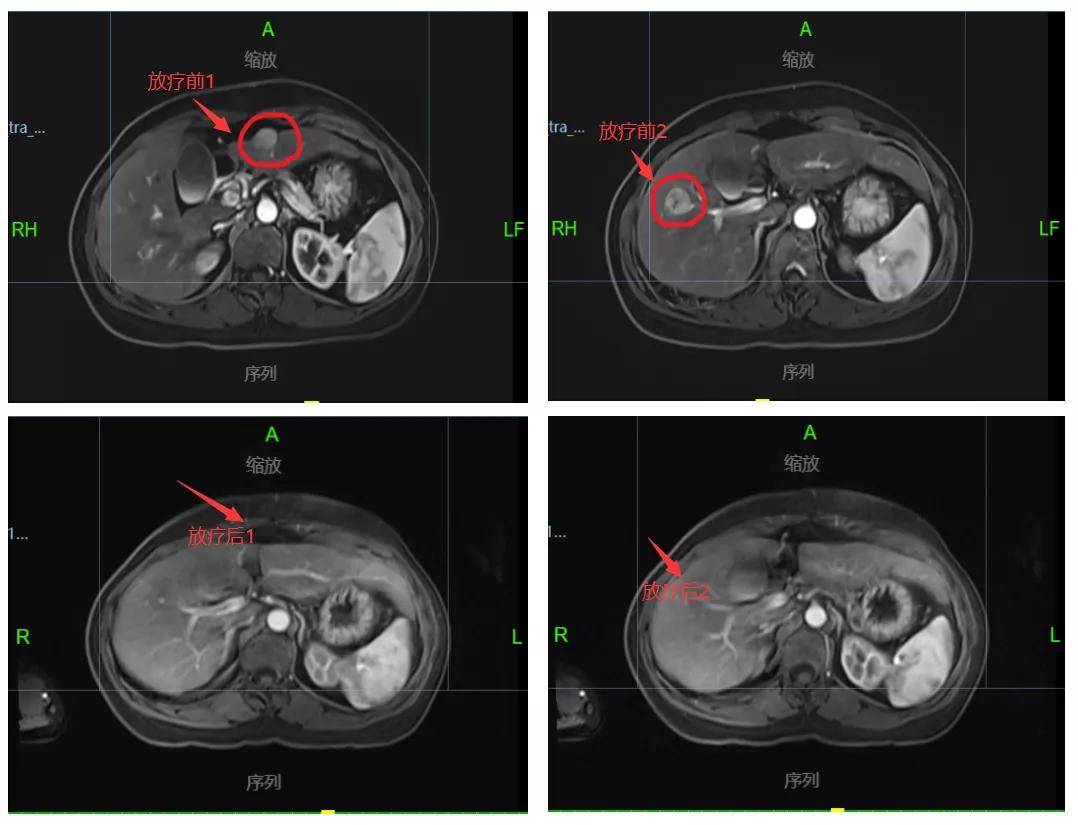

因上述症状持续存在,并逐渐加重,至广州中医药大学金沙洲医院国际肿瘤医疗中心(乘坐1-4号电梯到17楼)就诊,据病史资料及辅助检查,考虑为肝恶性肿瘤,经多学科肿瘤会诊讨论,排除治疗禁忌后行肝脏病灶立体定向放射治疗50Gy/10Gy/5f,治疗过程顺利无不适,期间予抗病毒、抑酸、护肝及对症治疗。

经过一个疗程的放射治疗,复查上腹部MRI:1.“肝癌综合治疗后”改变,病灶较前明显缩小。(肝S5内可见结节状异常信号影,T1WI呈低信号,T2WI、T2WI-FS呈稍高信号,DWI高b值呈高信号,ADC呈低信号,形态规则,边界清晰,最大者大小约为0.7cm×1.0cm,增强扫描病灶明显强化,病灶较前明显缩小。原S3、S2病灶未见显影,增强未见强化。